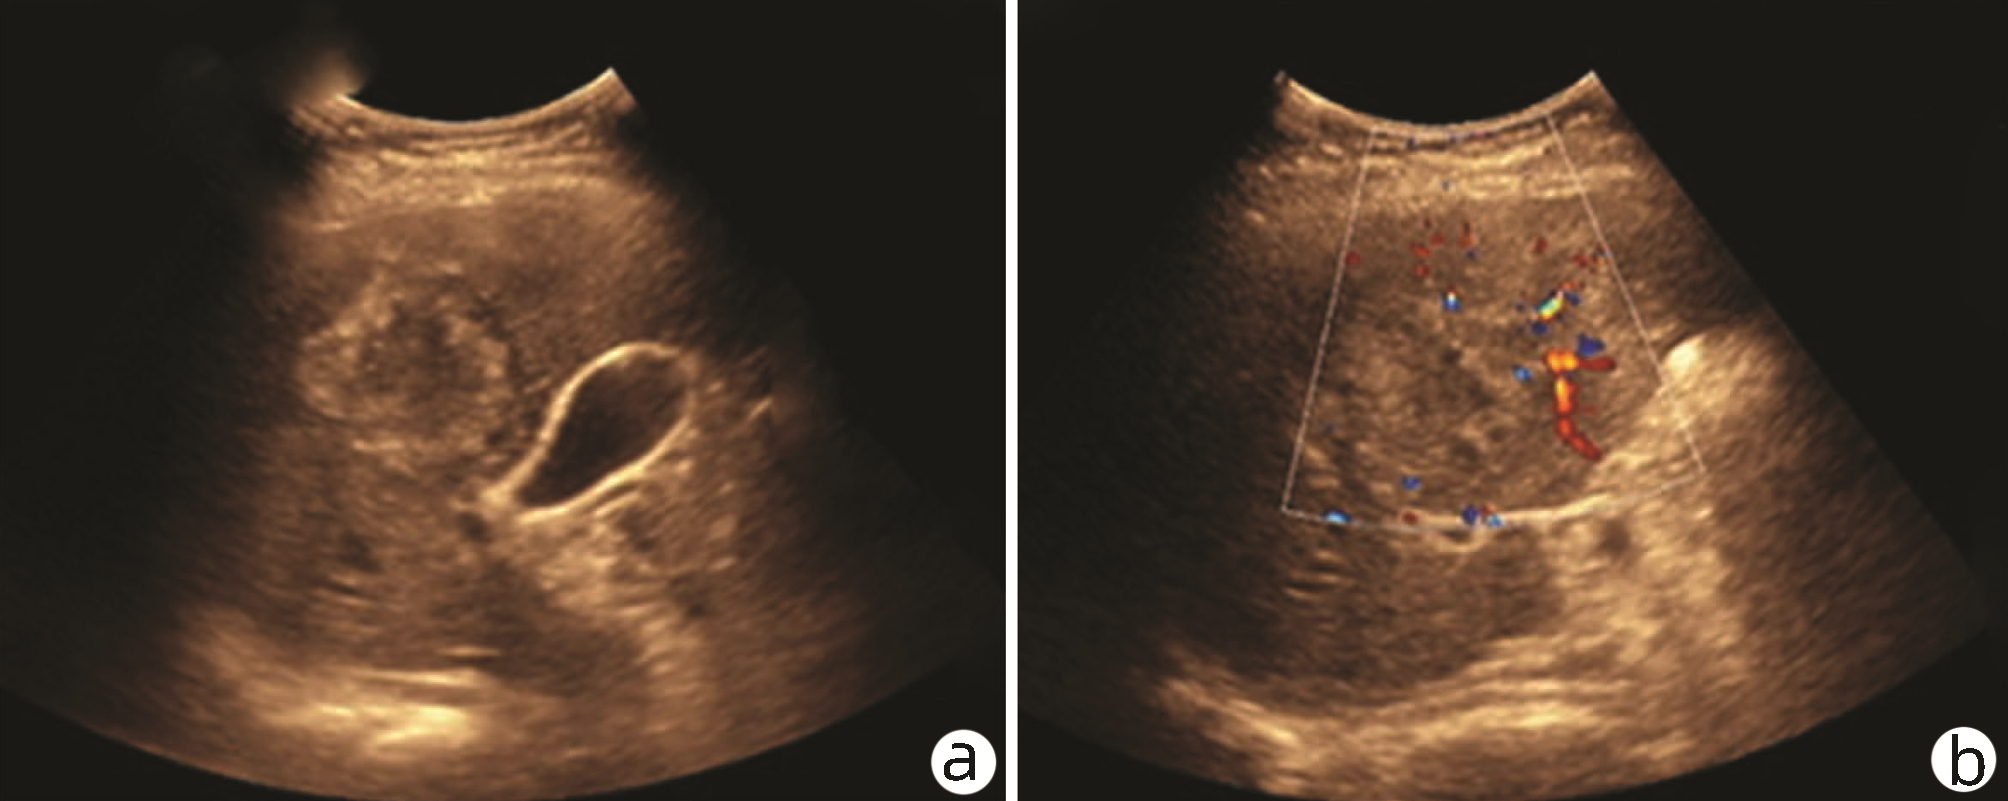

Carcinosarcoma of the liver: A case report